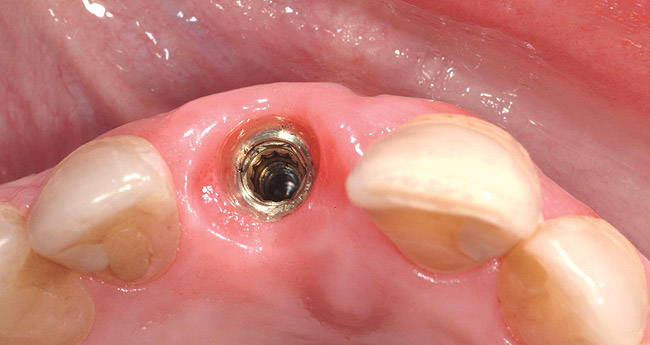

Figure 18  Occlusal view of four anterior maxillary implants with optimal peri-implant soft-tissue contours. Implant-level impressions of these implants were accomplished without incident.

Figure 18